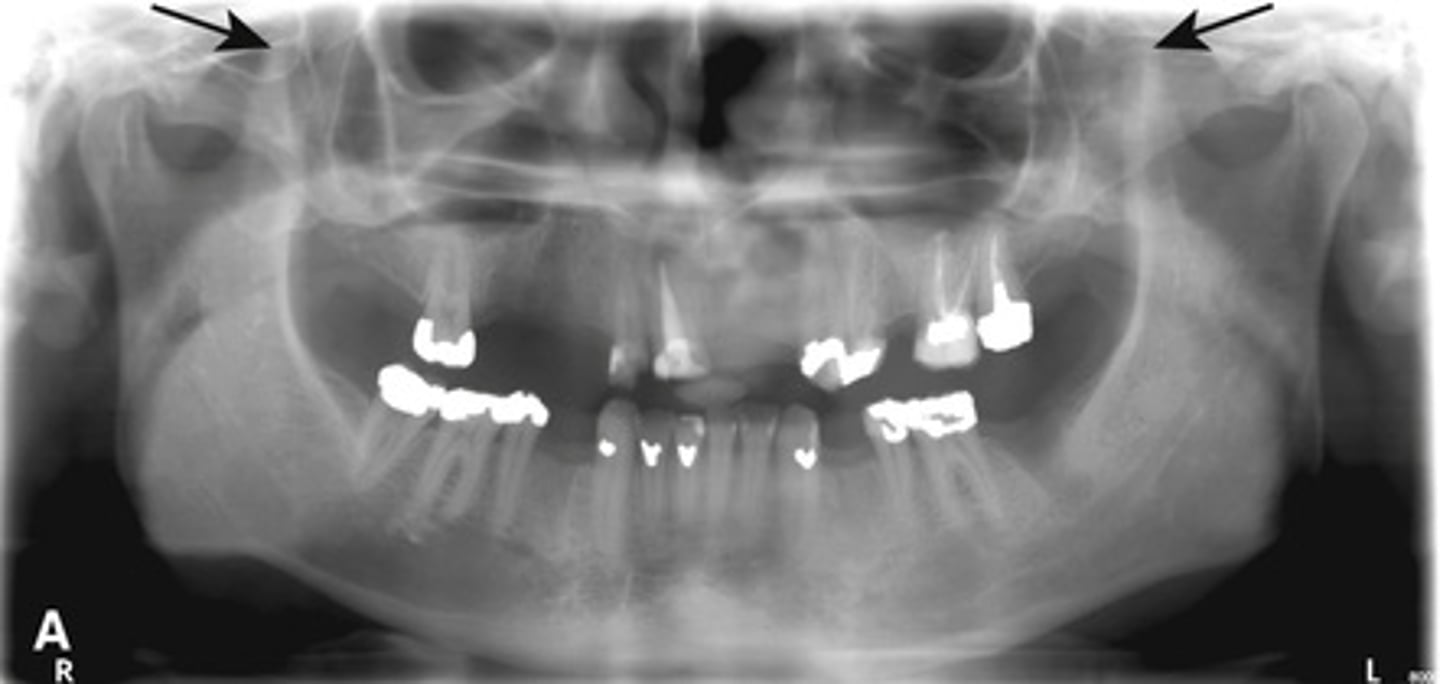

Root tip dislodged into the maxillary sinus.

You can see the PDL

How can you differentiate this from an antroliths in the maxillary sinus?

Root fragment dislodged into the maxillary sinus, this has implications for maxillary posterior extractions.